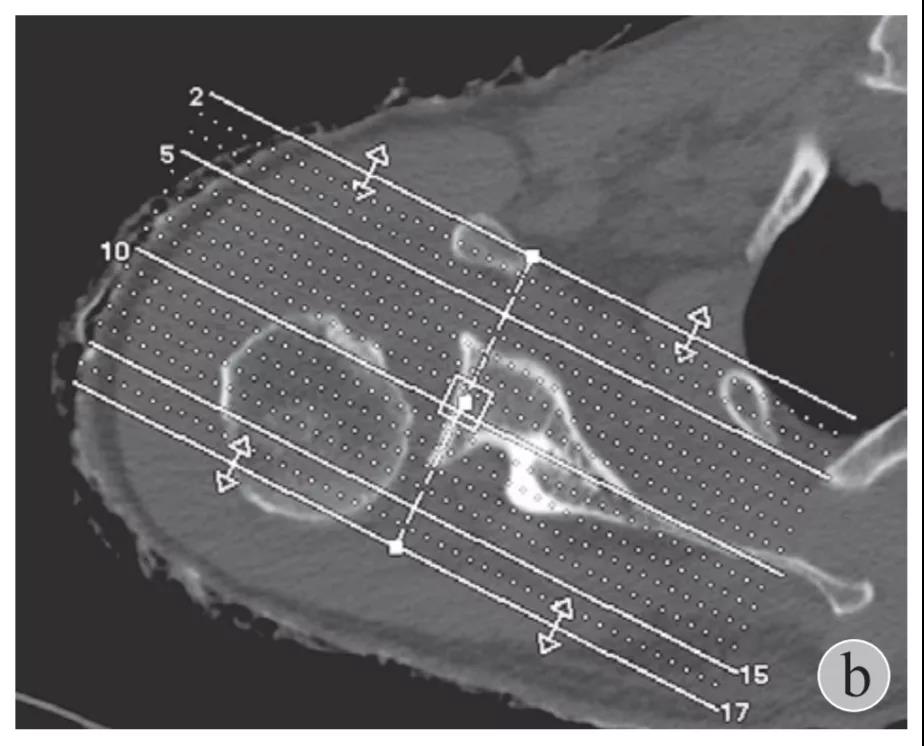

就诊我院后完善CT,诊断明确——左肩关节后脱位:

予以手法复位后拍片复查显示“灯泡征”消失,复位成功。讨论:肩关节后脱位在临床较为少见,特别是影像科经验不足很容易漏报,所以我们临床医生一定要自己仔细阅片,同时要结合体查来进行诊断,防止漏诊。肩关节后脱位时体查也有明显特征:肩关节前方明显变平,喙突较平时明显凸起容易触及,而肩关节后方明显丰满,上臂一般处于内旋内收位,无法主动外旋外展。肩关节后脱位的手法复位相对于前脱位的复位来说也比较容易。患者一般可以取坐位,助手自患侧腋下环抱患者稳定患者躯体,术者一手拉患肢上臂稍牵引内旋,一手自后方推顶肱骨头一般可以复位,如果单纯推顶无法复位也可以术者两手握住伤肢缓慢外展并沿肱骨纵轴牵引,然后逐渐外旋上臂即可复位。整复完成后可以把持患肢作肩关节各个方向的小幅度被动活动,防止肩关节粘连,肩关节后脱位的固定方法与肩关节前脱位的固定方法不同,应将患肢置于上臂外展、后伸、外旋位固定,即外展30度、后伸30度和轻度外旋位,用外展支架固定3周后,循序渐进开始肩关节功能康复。